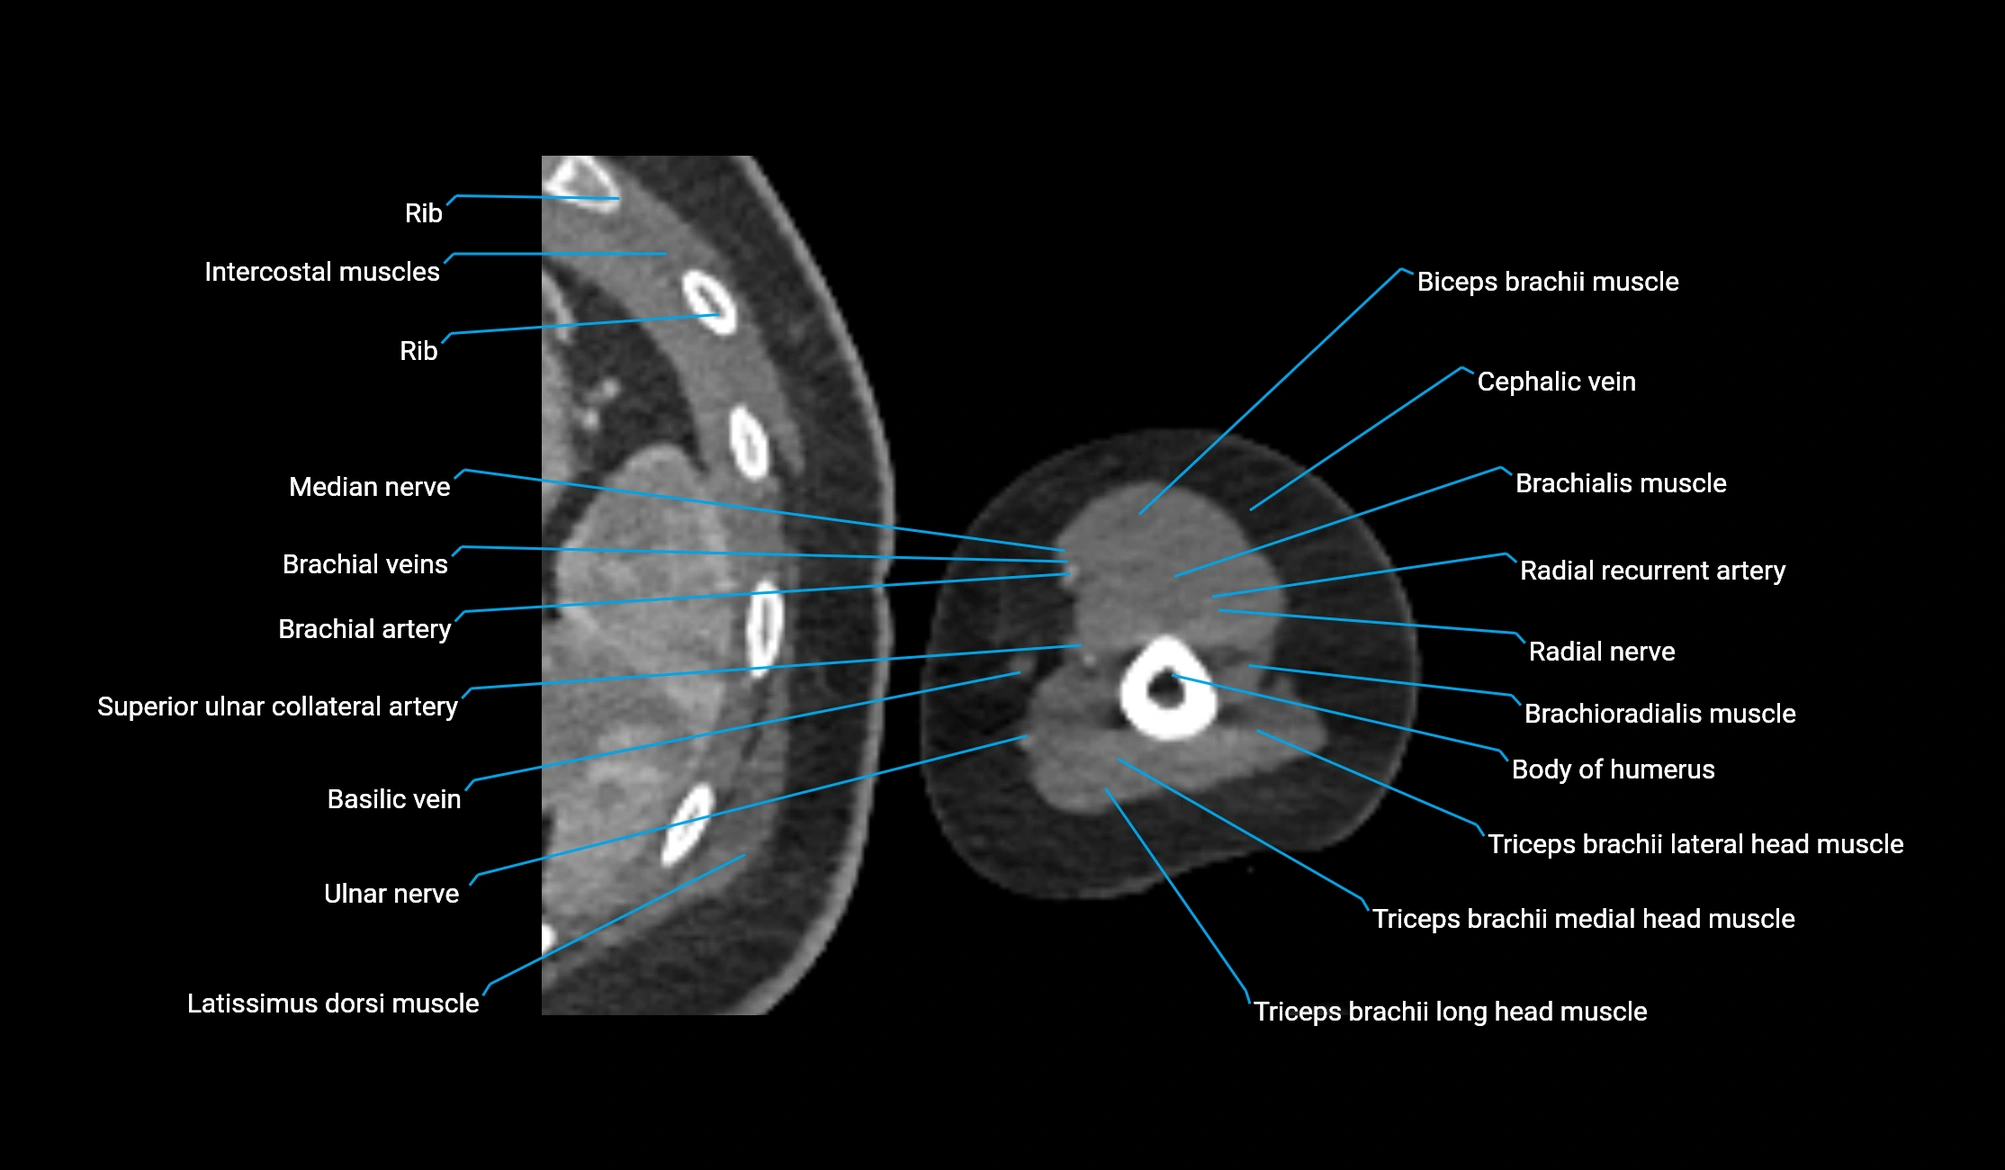

- Body of humerus

- Brachialis muscle

- Brachioradialis muscle

- Cephalic vein

- Extensor carpi radialis longus muscle

- Lateral head of triceps brachii muscle

- Long head of triceps brachii muscle

- Medial head of triceps brachii muscle

- Median nerve

- Radial nerve

- Radial recurrent artery

- Superior ulnar collateral artery

- Triceps brachii muscle